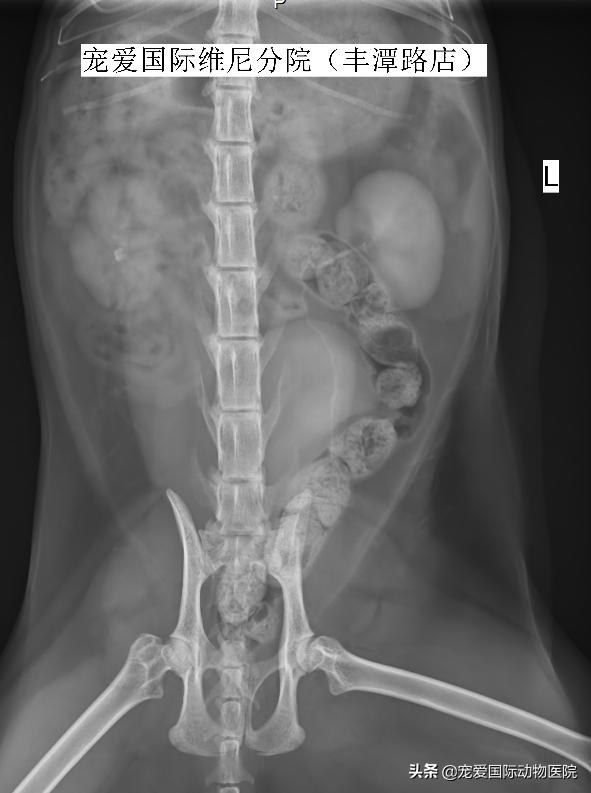

BCS4/9,被毛凌乱,脱毛严重,粘膜淡粉,左眼单侧第三眼睑增生,中度牙结石,心肺听诊尚可,腹部柔软,大量宿便,右侧肾区触诊有痛感。

生化检测见肌酐尿素氮升高

B超检测,见右侧肾盂扩张

内有一直径6MM结石

右侧肾结石,右侧输尿管堵塞